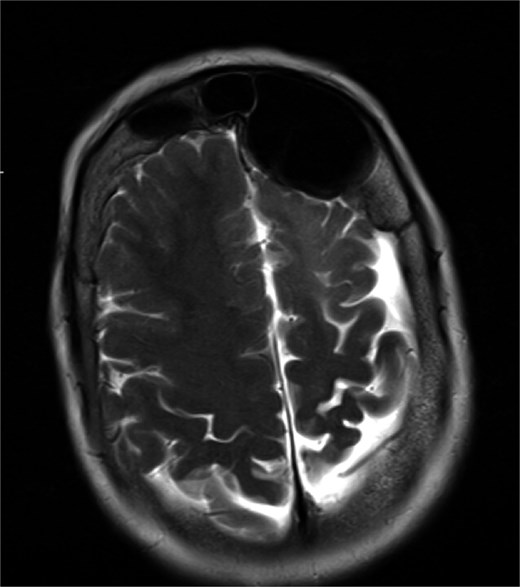

MRI demonstrated marked expansion of the left frontal sinus, consistent with PD, exerting a mass effect on the adjacent left frontal lobe and associated with a small area of increased T2-FLAIR signal intensity (Fig. 1). There was no evidence of compression of the lateral ventricle. However, mild prominence of the sulci and lateral ventricle on the left side suggested underlying parenchymal volume loss. No signs of hydrocephalus, midline shift, restricted diffusion, or susceptibility artifacts were identified. The optic nerve, optic chiasm, and optic tracts appeared normal. CT tomography confirmed these findings (Figs 2 and 3).

MRI showing enlarged left frontal sinus with mass effect on the frontal lobe.